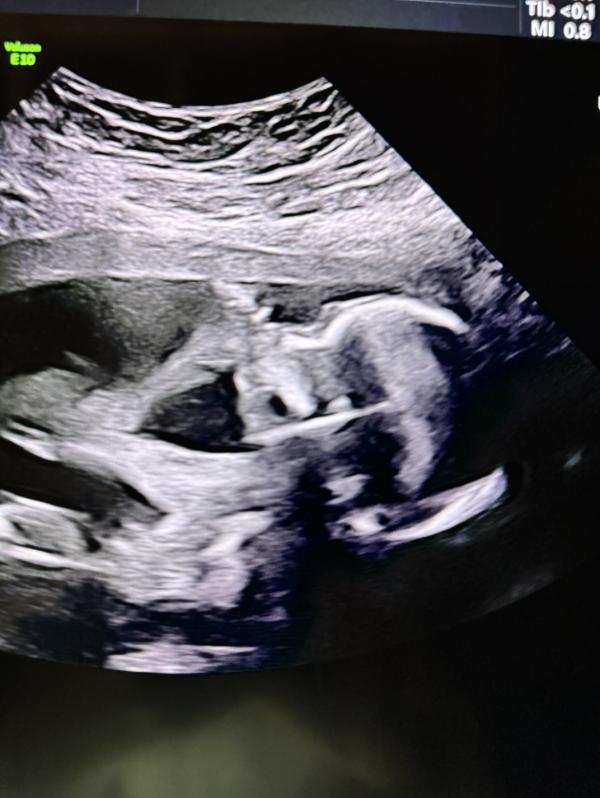

Развитие плода на 6 и 16 неделях беременности

6 недель и 16 недель, с такой маленькой капельки целый человечек, Аллагьума Барик